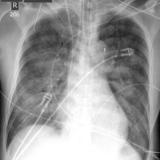

APE 3

Date: 11/05/2005

Views: 3886